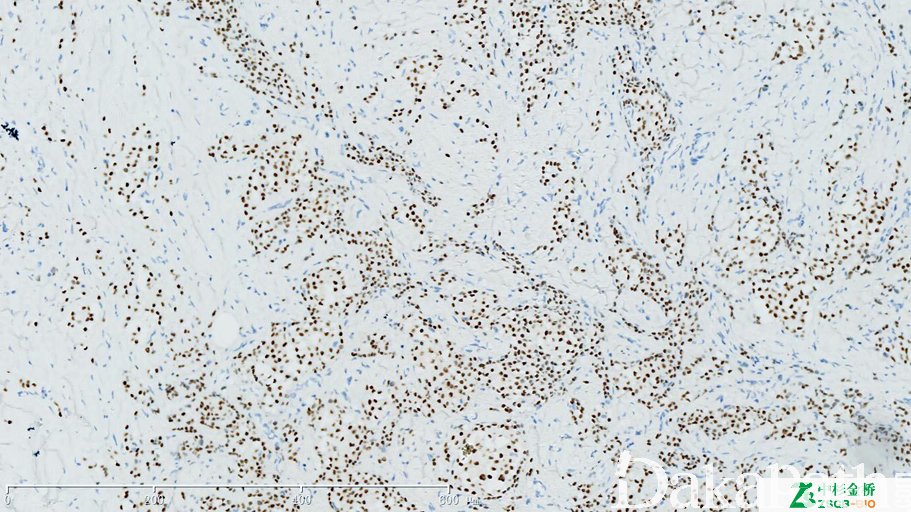

信号定位: 核着色,浆着色不计

几乎全部阳性(≥95%的病例阳性): 乳腺小管癌、乳腺乳头状癌、乳腺癌,腔 B 型、乳腺癌,腔 A 型、乳腺浸润性导管癌,伴小叶癌特征、乳腺乳头状瘤、乳头状血管内皮增生

通常阳性(<95%,≥75%的病例阳性): 血管纤维瘤,NOS、子宫内膜腺癌 I-II 级、高级别子宫内膜间质肉瘤、乳腺导管原位癌、乳腺筛状癌、乳腺浸润性癌,非特殊类型、卵巢 Brenner 瘤、卵巢浆液性癌、乳腺导管原位癌,低级别、乳腺小叶原位癌、性索间质肿瘤、乳腺浸润性小叶癌